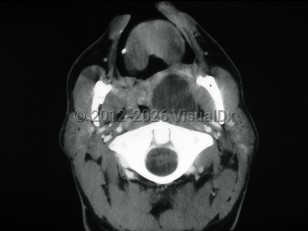

Peritonsillar abscess

Peritonsillar abscess, also known as quinsy, is a deep neck space infection characterized by a collection of pus in the peritonsillar space.

Patients present with a muffled voice, fever, sore throat, and dysphagia. There is deviation of the uvula to the unaffected side. Trismus and otalgia may be present. This infection usually affects young adults, but all ages can be affected. Older adults may have subtler symptoms. Laboratory findings include leukocytosis. Treatment consists of antibiotic therapy and surgical drainage.